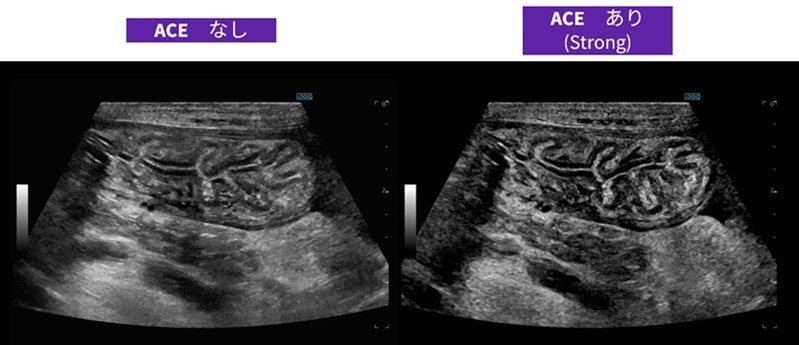

● CPU/GPUハードウェアを基盤に膨大なデータをリアルタイム再構成、全ピクセルを最適化するcSound Imageformerや位相のゆがみを判断する高画質化技術ACEを搭載することで、画像の精度の向上を実現。

フラグシップモデルのLOGIQ E10シリーズと同じcSound Imageformerが搭載されており、近位部から深部に至るまで均一なイメージを提供するために全視野・全深度フルフォーカスを実現しています。位相のゆがみを判断する高画質化技術ACEの搭載によりさらに深部まで高画質に描出することができ、体格のよい被験者においても明瞭な画像を実現できるようになりました。